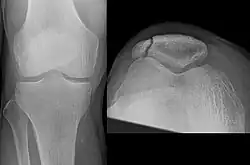

-

Vertical patella fracture

The patella can break in various ways depending on the way it is injured, and into two or more pieces.[1] Types include transverse, the most common, with one fracture line;[5] marginal; osteochondral; and the rare vertical type, or stellate, where a direct compression force gives rise to a comminuted pattern.[5][7] Patella fractures can be further classified as displaced, where the broken ends of bone do not line up correctly and separate by more than 2mm, or undisplaced and stable where pieces of bone remain in contact with each other.[1][7] If fragments of patella bone stick out from the skin it is known as an open patella fracture, and closed if the overlying skin is intact.[1]